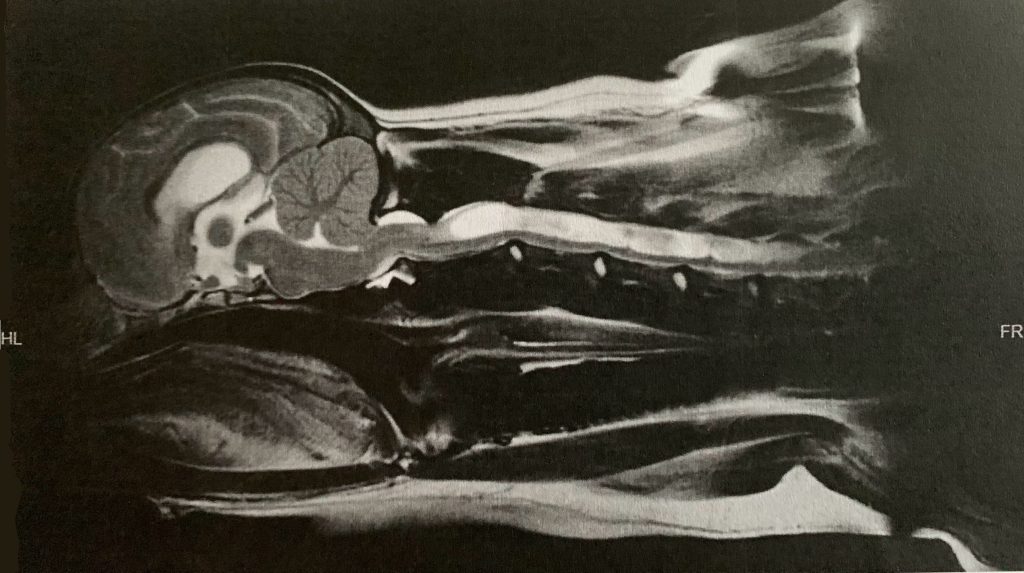

A “clear” scan: grading is CM2/SM0c. The dog has mild CM, no syrinx, no CCD, no dorsal banding, normal ventricles, and only mild medullary elevation.

A severely affected dog: grading is CM2/SM2a. The syrinx is 8mm. The dog also has significant dorsal banding, medullary elevation, and ventricular dilation.